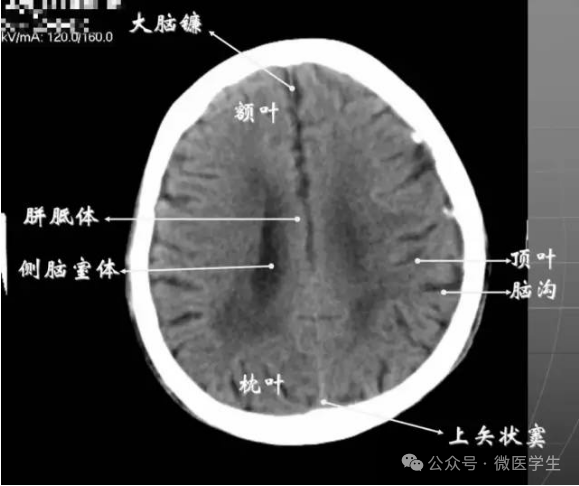

由额、颞、枕叶构成,两侧侧脑室体部之间为透明隔,外侧为尾状核和体部。侧脑室后角(枕角)可不对称,室内可见脉络丛钙化。中线处可见大脑纵裂池和大脑镰。

内侧壁侧脑室体部被胼胝体分开,侧脑室体部的外方为顶叶,顶枕沟及中央沟将大脑为为额、顶、枕叶。

在胼胝体和侧脑室上方,大脑镰自前向后贯穿中线。白质部分为半卵圆中心,额叶范围缩小,顶叶所占比例扩大,枕叶基本消失。

- 半卵圆中心:位于胼胝体上方,由左右大脑半球髓质形成的有髓纤维,对称位于大脑镰两侧区域。

已近颅顶,大脑镰清晰可见,其旁的脑灰质和脑沟十分清楚。顶叶较小,额叶较小。

- 放射冠:是内囊到大脑皮质间的放射状纤维白质。